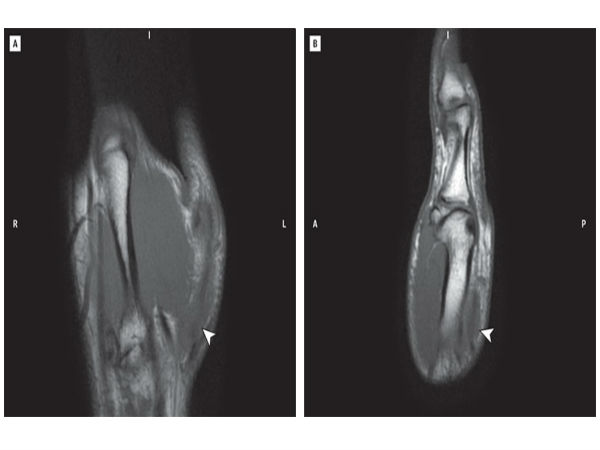

அந்த தம்பிக்கு 29 வயசு, தலைவரு சோறு தண்ணீ சாப்பிடுறாரோ இல்லயோ 24 நாலு மணி நேரமும் கேண்டி க்ரஷ் விளையாடிட்டே இருந்தாராம். இப்பிடியே விடாம 8 வாரம் விளையாட, தன் கட்டை விரல் செயல் இழந்தததை அறிந்த பின் தான் விளையாடுவதை நிறுத்தி விட்டு ஆஸ்பத்திரிக்கு ஓடி இருக்கிறார்.

வீட்டுல கழுவி கழுவி ஊத்தினாங்களோ இல்லயோ, டாக்டர்கள் கடுப்பாகி இருக்கிறார்கள், கை தசையில் முறிவு ஏற்பட்டு உள்ளது கூட உணராமல், இத்தனை நாளாக வலிப்பது கூட தெரியாமல் பைத்தியமா விளையாடினாருல, தேவை தான்..!